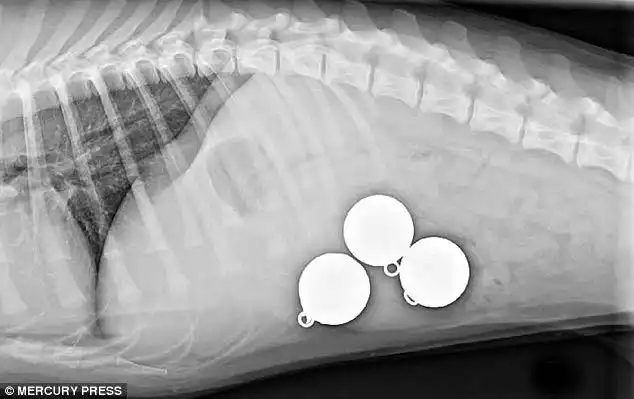

Доберман Зевс, съевший 26 мячей для гольфа

Все 26 мячей извлеченные из его живота